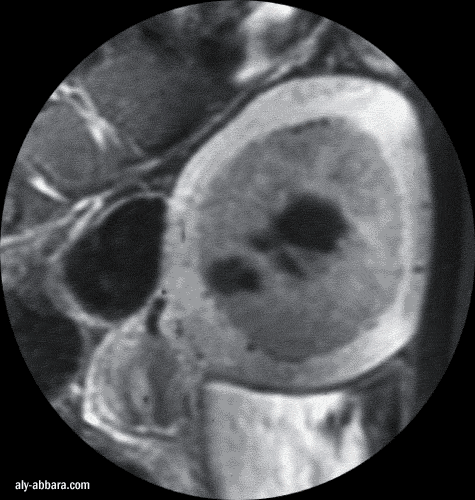

IRM (Imagerie par Résonance

Magnétique) - coupe sagittale de l'utérus

Fibrome utérin (myome) sous muqueux endocavitaire avec nécrobiose

aseptique

à l'origine de multiple foyers kystiques au sein du fibrome

Ce fibrome est

à l'origine de ménorragie et d'anémie